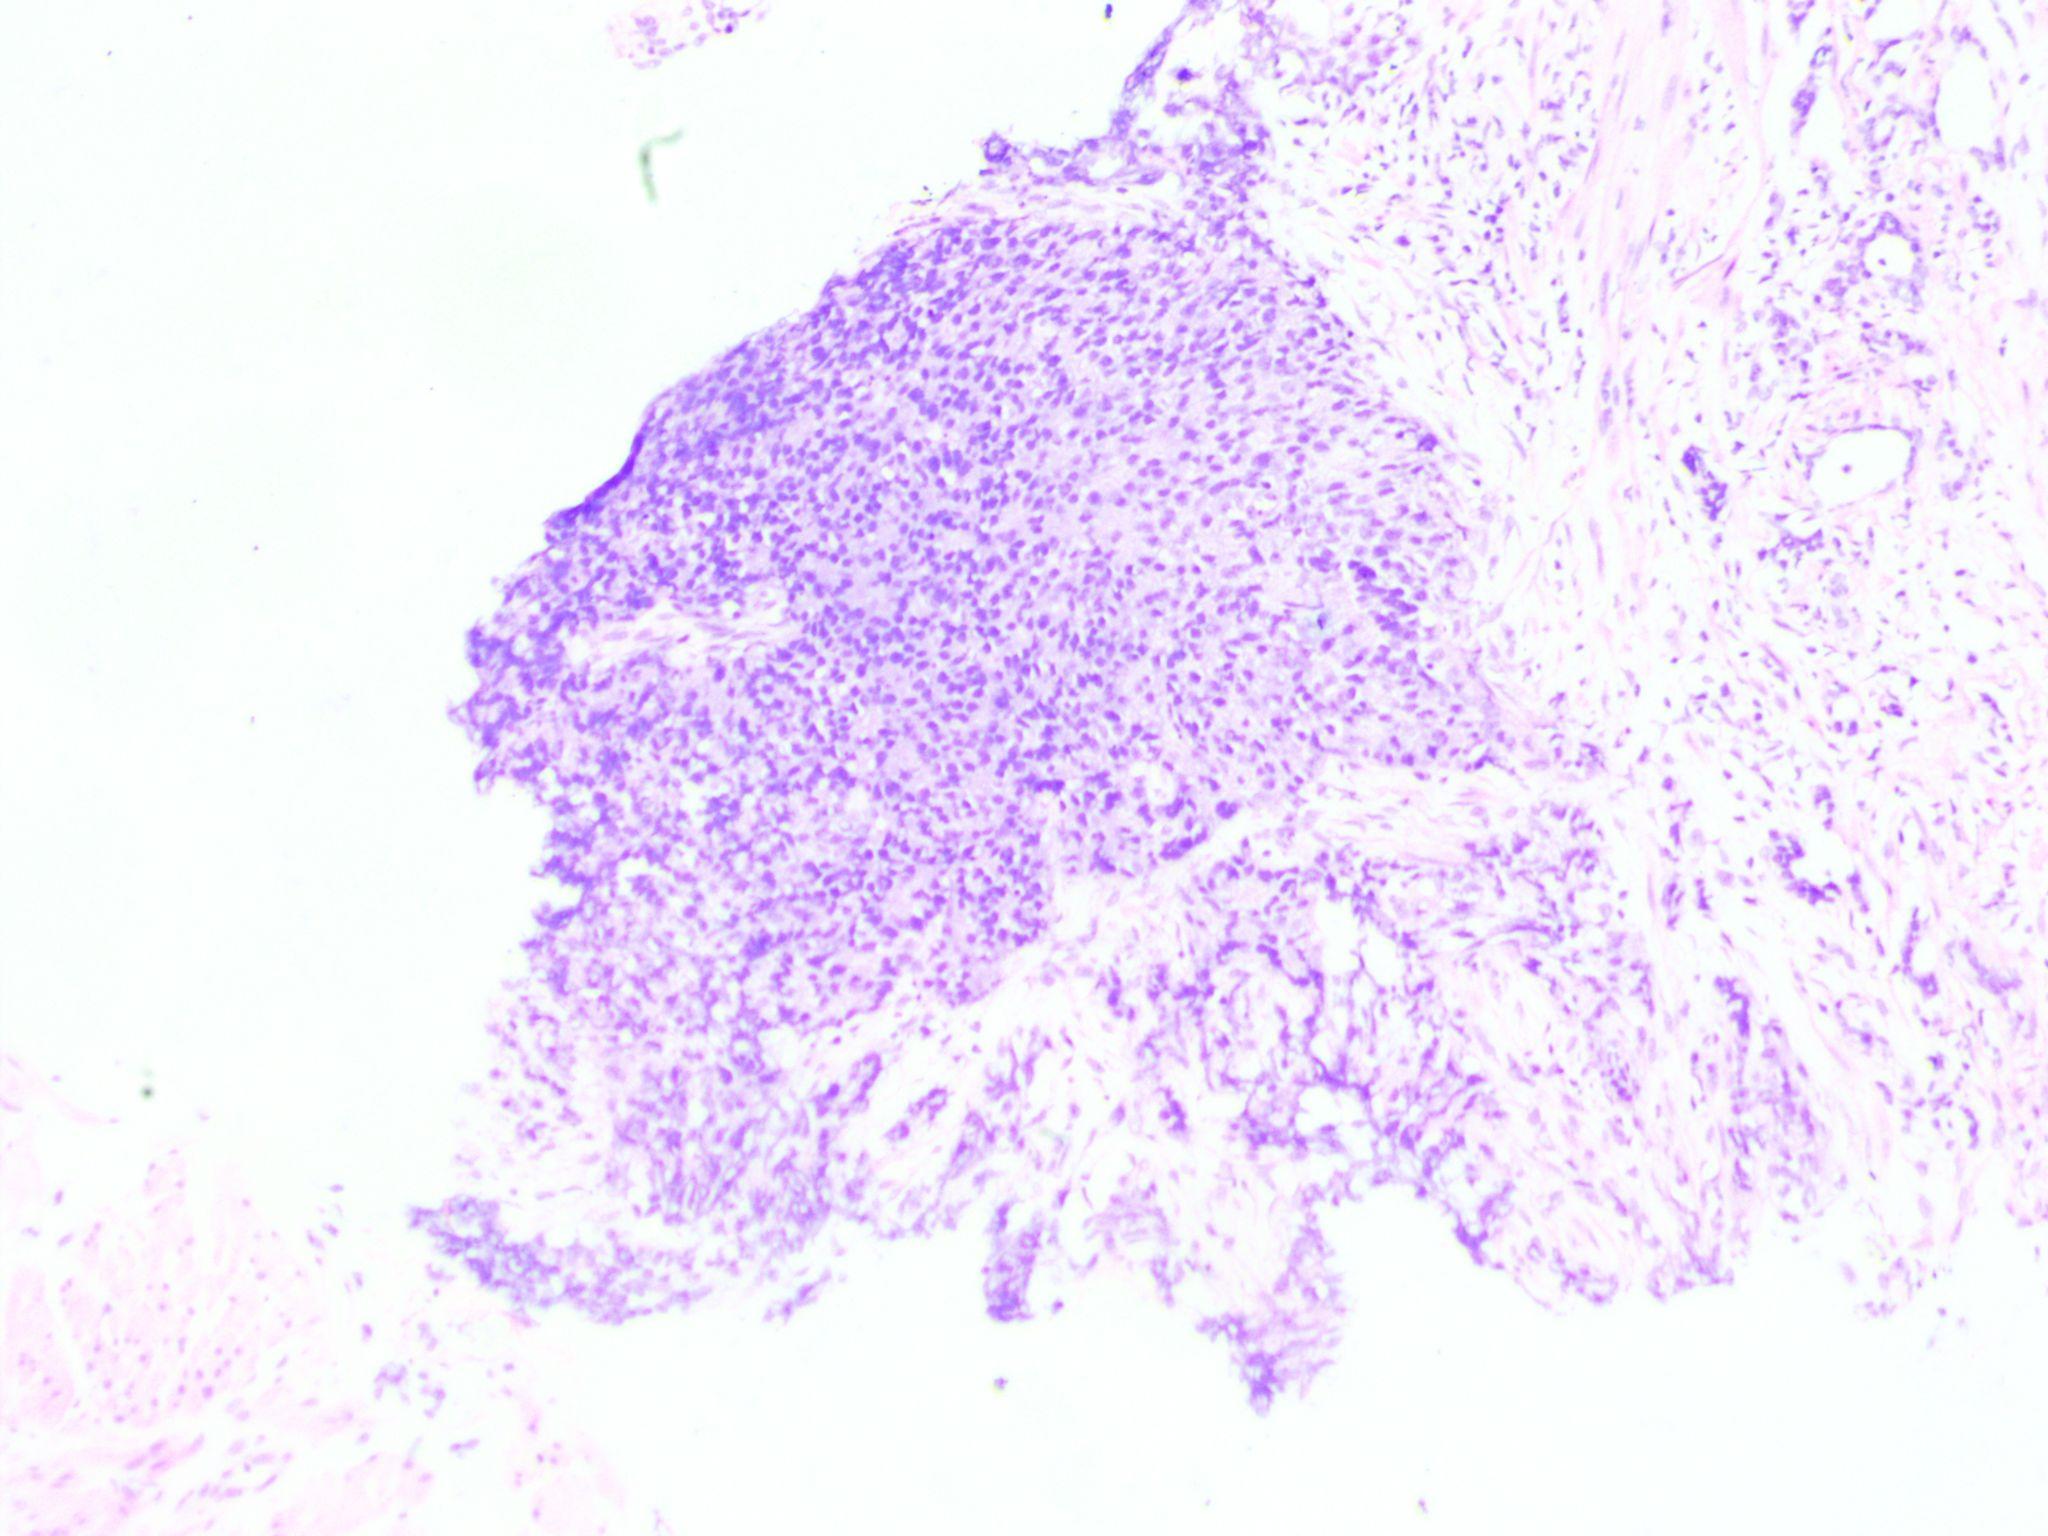

A transurethral biopsy of the mass was performed. Histopathological analysis revealed clusters of small round blue cells infiltrating the prostatic tissue. Immunohistochemistry study revealed a high degree of CD99 positivity and diagnosis of prostatic PNET was made.

Histopathological characteristics are crucial in making the diagnosis of a prostatic PNET. PNET appears as a mass of small, round undifferentiated cells cluster densely packed in a lobulated, nest-like, or flaky pattern under a light microscope. Over 90% of PNETs have the EWS-FLI1 fusion gene positive and exhibit a translocation between chromosomes 11 and 22's long arms. PNET's characteristic round cells react to antiCD99 antibodies (Mic-2).[8] A large number of cases follow the diagnosis scheme developed by Schmidt et al, It involves the existence of Homer-Wright rosettes and/or the expression of two or more neural markers.[9] In our case CD99 IHC marker was positive in tumor cells. Radiotherapy, chemotherapy, and surgery combined can be a successful treatment plan for PNET of the prostate. It is common practice to recommend the chemotherapeutic drugs vincristine, doxorubicin, cyclophosphamide, etoposide, and ifosfamide.[8] In 177 patients with localized Ewing's sarcoma, Dunst found that radiotherapy was equally effective in terms of overall survival as surgery or a combination of surgery and radiotherapy. For localized PNET of the prostate, chemotherapy is a potentially useful treatment option, albeit a standard protocol has not yet been established.[10]